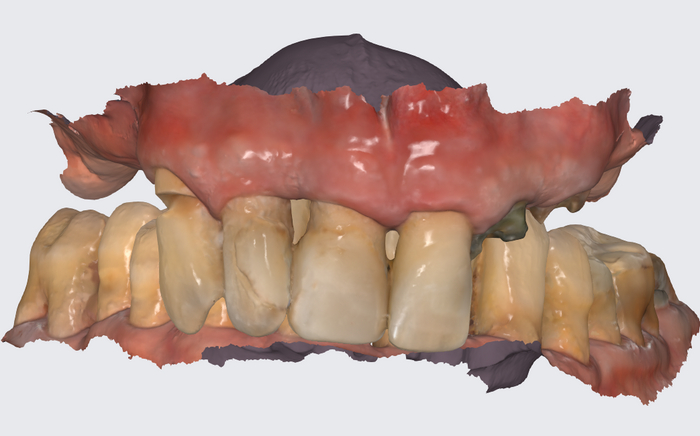

Уже введена в эксплуатацию новая аппаратура, позволяющая находить истинный прикус человека, нам остаётся лишь зафиксировать это положение:

Помещаем протез в полость рта, "прикручиваем" к имплантатам. Очень хорошо попали с первого же раза в комфортное положение.

Фотографируем пациента.

Протез снимается и отправляется обратно в лабораторию - техник учтёт малейшие замечания и в субботу получим протез временный в окончательном варианте.

Временный протез "всё на 4-х", постановка на воске